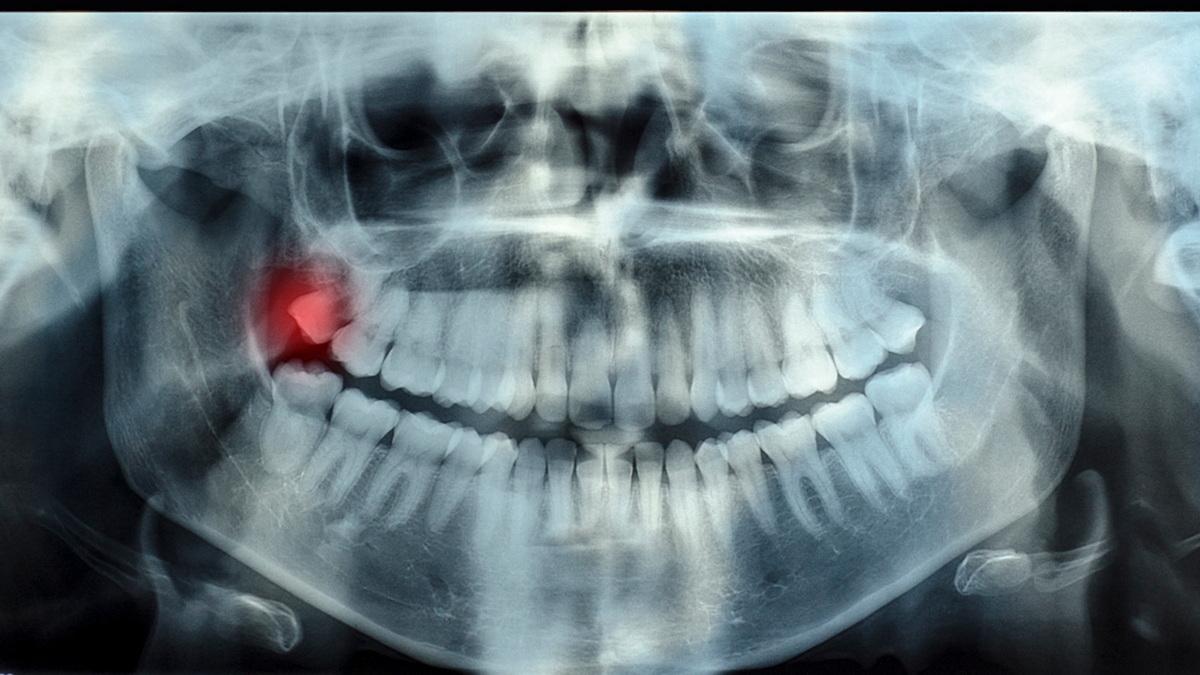

Diese Positionen werden in der Regel durch Panoramaröntgen oder eine zahnärztliche Tomographie (3D-Bildgebung) eindeutig bestimmt. Entsprechend werden die Behandlungsentscheidungen getroffen. In den Jimer Dental Clinics verwenden wir unsere modernen Panoramaröntgen- und Dentaltomographiegeräte (3D-Bildgebung), um eine detaillierte Visualisierung der Weisheitszähne im Knochen und ihrer Nähe zu den Nachbarzähnen zu ermöglichen und so eine wirksame Diagnose und Behandlung zu ermöglichen.

Drücken diese retinierten Zähne auf Nachbarzähne und liegen in der Nähe des Kiefernervs, müssen sie von einem Kieferchirurgen operativ entfernt werden, um Probleme zu vermeiden. Während der Weisheitszahnentfernung in den Jimer Dental Clinics erfolgt eine detaillierte Untersuchung und Diagnose mithilfe modernster Bildgebungsverfahren wie der 3D-Volumentomographie (CBCT) und Panoramaröntgen. Anhand radiologischer Bilder beurteilt der Kieferchirurg die Position des Zahns im Kieferknochen, seine Nähe zu den Nerven und Nachbarzähnen millimetergenau und erstellt anschließend den Operationsplan. Die Operationsplanung, insbesondere bei teilweise oder vollständig retinierten Weisheitszähnen, wird dank dieser fortschrittlichen Bildgebung deutlich sicherer.

Zuerst werden die Lage des Zahns, sein Abstand zum umliegenden Gewebe und seine Beziehung zu den Nerven gründlich untersucht. Es wird eine Panorama-Röntgenaufnahme oder, falls erforderlich, eine zahnärztliche Computertomographie (CT) angefertigt. Der Kieferchirurg wertet anschließend alle Bilder aus und erstellt einen Plan, der entscheidet, ob der Zahn durch einfache Extraktion oder chirurgische Entfernung entfernt wird.

Eine frühzeitige Diagnose und radiologische Bildgebung (Panoramaröntgen oder dentale CT-Aufnahme) können die Position des Zahns klären. Die Beurteilung muss von einem Zahnarzt und Kieferchirurgen durchgeführt werden. Wenn der Zahnarzt oder Kieferchirurg es für angebracht hält, wird eine chirurgische Entfernung empfohlen.